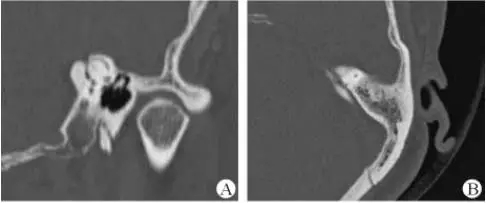

1、上半規管裂綜合征

內耳結構非常微妙。即使是內耳中大頭針樣的孔洞也能造成平衡失調?;颊叱32桓疫M行如走路或轉頭的日?;顒印4撕币娂膊?,醫學專家預估至少影響著人口的1%??稍斐蓯盒?,眩暈以及對噪聲極高的敏感性。病人還常常抱怨他們能聽到血管跳動的聲音。其中一位患者曾告訴耳科專家,他都能聽到自己轉動眼睛的聲音。

診斷及治療

醫生若懷疑此病將會安排內耳CT掃描。在大多數案例中,一旦此病被耳鼻喉科醫生或其它聽力健康專家確診,則可實行手術治療。外科手術風險包含聽力損失以及神經損傷;重建及復原需內耳的治療以及大腦的重塑。